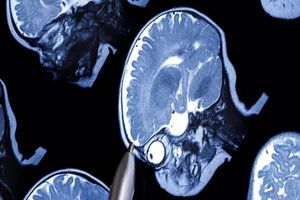

اسکن DT-MRI

این نوآوری از فرآیندی منفعت گیری میکند که اسکنهای MRI تنسور پخش وزنی(DT-MRI) از مغز را طبقهبندی میکند که به یک فناوری تخصصی اشاره دارد که نحوه حرکت آب در طول مسیرهای ماده سفید در اندام بدن را تشخیص میدهد.

گرگوری بارنز، استاد عصب شناسی و مدیر مرکز اوتیسم کودکان نورتون در لوئیزویل و یکی از نویسندگان این مطالعه تازه میگوید: اوتیسم در درجه اول، بیماری اتصالات نامناسب در مغز است. روش DT-MRI این ارتباطات غیرطبیعی همانند اختلال در ارتباطات اجتماعی و رفتارهای تکراری را ثبت میکند که تبدیل علائمی میبشود که کودکان مبتلا به اوتیسم زیاد تر دارند.

این تکنیک هوش مصنوعی با جمعآوری سیگنالهای تصویربرداری که قوت ربط بین نواحی گوناگون مغز را مشخص می کند، کار میکند. اینها از طریق منفعت گیری از اسکن DT-MRI شناسایی خواهد شد که به محققان اجازه میدهد تصاویر بافت مغز را جدا کنند. سپس یک برنامه یادگیری ماشینی به قیاس الگوهای نشانگر در مغز کودکان اوتیسمی با مغزهایی که به درستی شکل گرفتهاند، ادامه میدهد.

تیم تحقیقاتی برای این مطالعه از اسکنهای مغزی DT-MRI به دست آمده از یک مجموعه داده منفعت گیری کردند که شامل اسکن مغزی ۲۲۶ کودک ۲۴ تا ۴۸ ماهه می بود که از بین آنها ۱۲۶ کودک مبتلا به اوتیسم و ۱۰۰ کودک غیر اوتیسمی بودند.